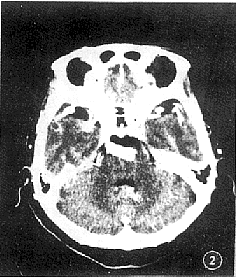

例2 女性,70岁,因头晕伴左面部麻木1周来诊。既往高血压病史20年。体检无阳性所见。头部CT增强扫描,见基底动脉异常扩张延长,达鞍上池层面,动脉直径达1.0 cm(图2,3)。CT诊断:基底动脉延长扩张症。

图2 增强扫描,见基底动脉延长、扩张,直径达1.0 cm